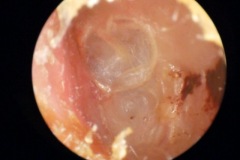

Cholesteatoma Clinical

Perforation